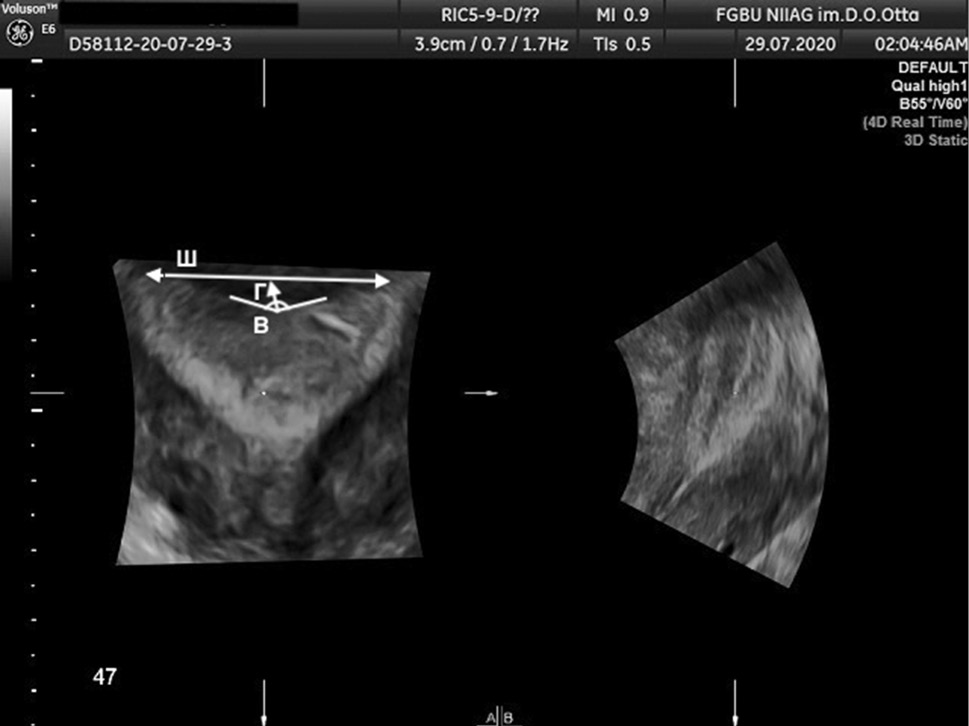

The AFS proposed to assess parameters, such as Г, cavity indentation; Ш, uterine cavity width; and B, angle of cavity indentation (Figs. 1–4).

Fig. 1. 3D ultrasound reconstruction of the uterine cavity: subseptate uterus, where Ш, uterine cavity width; Г, cavity indentation; B, angle of cavity indentation (86°)

Рис. 1. Ультразвуковая 3D-реконструкция полости матки — внутриматочная перегородка: Ш — ширина полости матки; Г — глубина вдавления полости матки; угол В — угол вдавления полости (86°)

Uterine septum is diagnosed using the following indicators: Г ≥15 mm, angle B <90º, while uterus arcuate is diagnosed using the following indicators: D ≥10 mm, but <15 mm and angle B >90° [11].